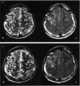

Surgical transection

The fornix (meaning "arch" in Latin) is a C-shaped bundle of nerve fibers in the brain that acts as the major output tract of the hippocampus. The fornix also carries some afferent fibers to the hippocampus from structures in the diencephalon and basal forebrain. [Source: Wikipedia ]